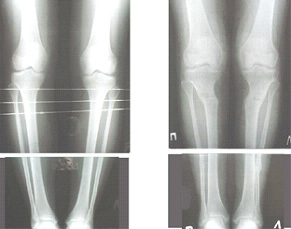

Ещё картинка - схема. Хотя у Соломина всё написано.

Вот ещё картинки, которые отправлял в Ортопод. Коррекция кривизны и удлинение на 3 см.